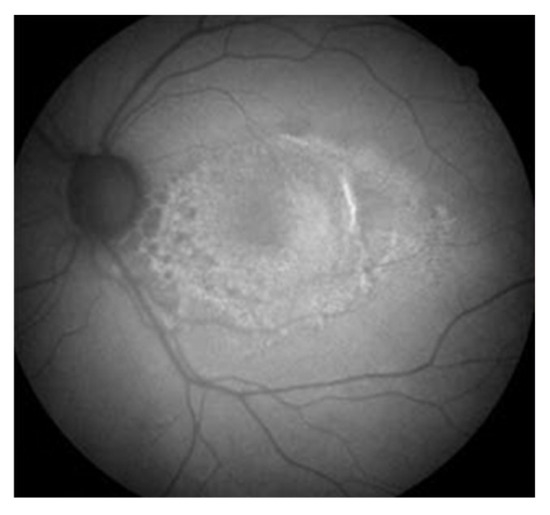

- Orellana-Rios, J.; Yokoyama, S.; Agee, J.M.; Challa, N.; Freund, K.B.; Yannuzzi, L.A.; Smith, R.T. Quantitative Fundus Autofluorescence in Non-Neovascular Age-Related Macular Degeneration. Ophthalmic Surg. Lasers Imaging Retin. 2018, 49, S34–S42. [Google Scholar] [CrossRef]